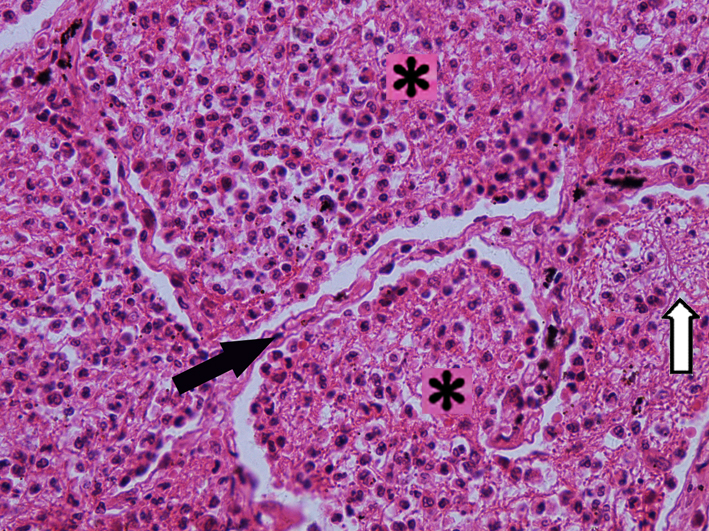

5.Hepatocellular carcinoma